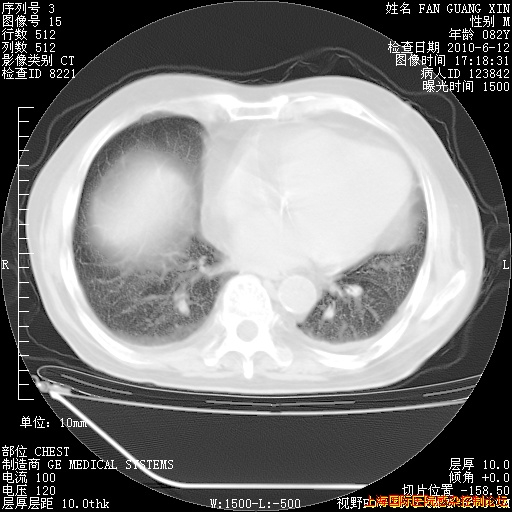

今天复查CT

今天CT

整整相隔30天的肺部CT好像有所好转啊。甲强龙减量第3天,需要观察体温。